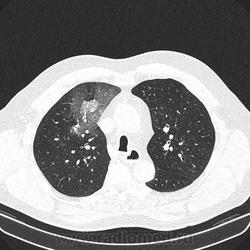

Альвеолярное кровоизлияние.

Полисегментарная пневмония.

оказалось ТЭЛА.

эту пневмонию вылечили, через некоторое время пациент поступил с подобной картиной в другом легком.

потом нашли тромб в артериях н/конечностей.